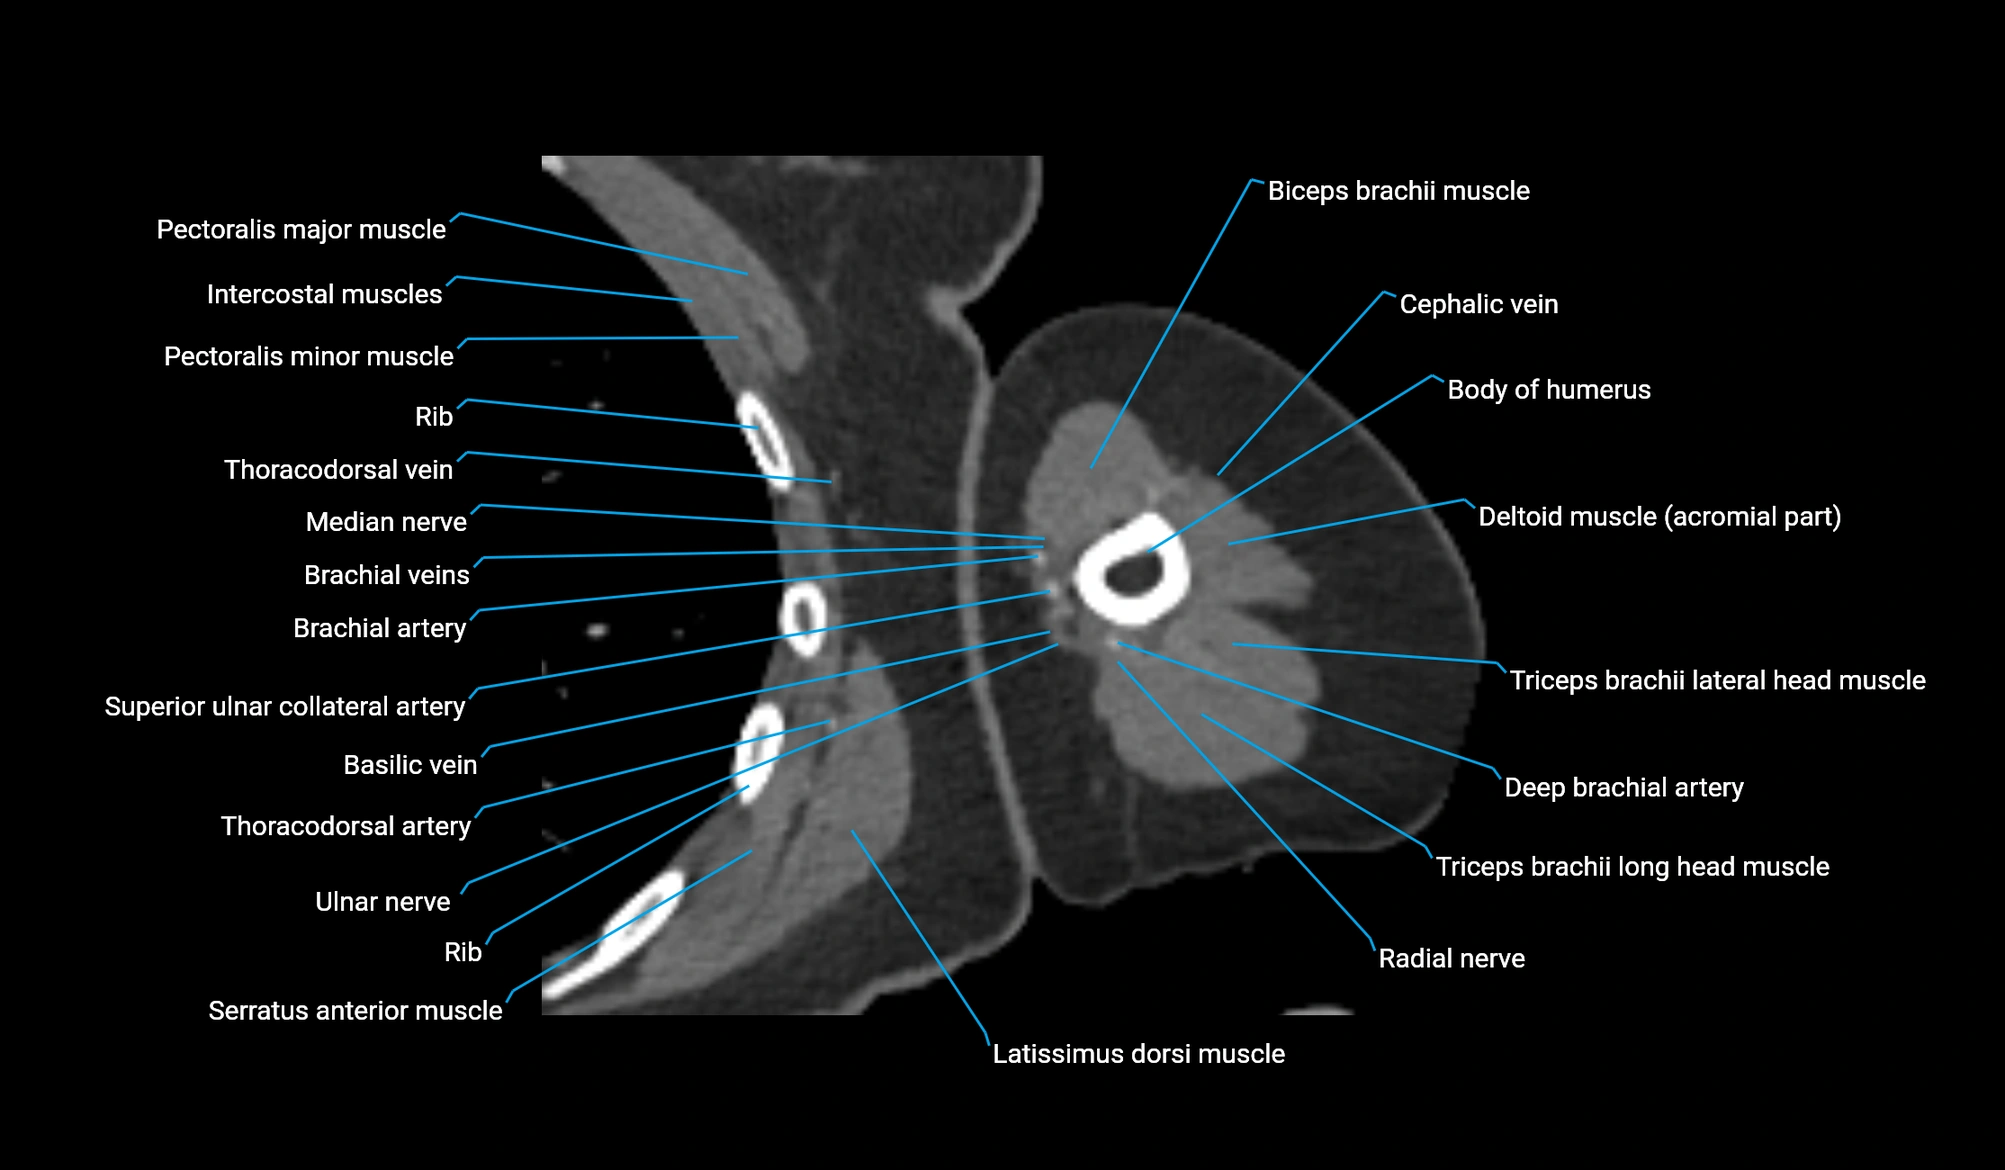

- Biceps brachii muscle

- Body of humerus

- Cephalic vein

- Clavicular part of deltoid muscle

- Deep brachial artery

- Deltoid muscle

- Long head of triceps brachii muscle

- Lateral head of triceps brachii muscle

- Median nerve

- Pectoralis major muscle

- Pectoralis minor muscle

- Radial nerve

- Superior ulnar collateral artery

- Thoracodorsal artery